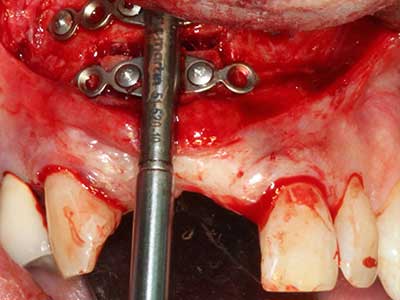

Indikation: Bone Splitting

Knochengewebe ist nicht nur rein mineralisch, sondern auch in wesentlichen Anteilen aus Kollagenfasern aufgebaut. Dies gewährleistet neben einer guten Druckfestigkeit eine gewisse Flexibilität, welche für die Durchführung von Augmentationen genutzt werden kann. Bei der klassischen Expansionsplastik im Sinne eines Bone Splittings wird der atrophierte Kieferkamm in seiner Längsachse gespalten und nach Erreichen einer ausreichenden Osteotomietiefe vorsichtig aufgedehnt (Abb. 13-16), idealerweise ohne den Kiefer wesentlich zu deperiostieren (Brugnami, Caiazzo et al. 2014, Stricker, Fleiner et al. 2014). Bewährt haben sich Schrauben- und Plattensysteme mit zunehmender Expansionsdistanz, um die beiden Knochenlamellen unterhalb der Bruchschwelle voneinander zu distanzieren. In der Regel werden Restknochenbreiten von mindestens 3-4 mm gefordert (Chiapasco, Zaniboni et al. 2006), um eine ausreichende Flexibilität und knöcherne Bedeckung der einzubringenden Implantate zu gewährleisten. Ggf. kann eine ein- oder beidseitige vertikale Entlastungsosteotomie die Flexibilität verbessern. Als Alternative zur klassischen Technik wurde eine Kombination mit weiteren augmentativen Techniken vor allem auf der bukkalen Seite beschrieben.

Mittels Piezosägen erfolgt die Anlage des Splittings besonders schonend und ohne wesentliche Dimensionsverluste, so dass sich keine signifikanten Unterschiede von Implantaten im gesplitteten Kiefer im Vergleich zum nicht defizitären Alveolarkamm gezeigt haben (Chiapasco, Zaniboni et al. 2006, Danza, Guidi et al. 2009). Gerade beim lokal begrenzten und tiefen Splitting ist jedoch stets auf eine ausreichende Wasserkühlung zu achten, um thermische Belastungen in den apikalen Osteotomiebereichen zu vermeiden.